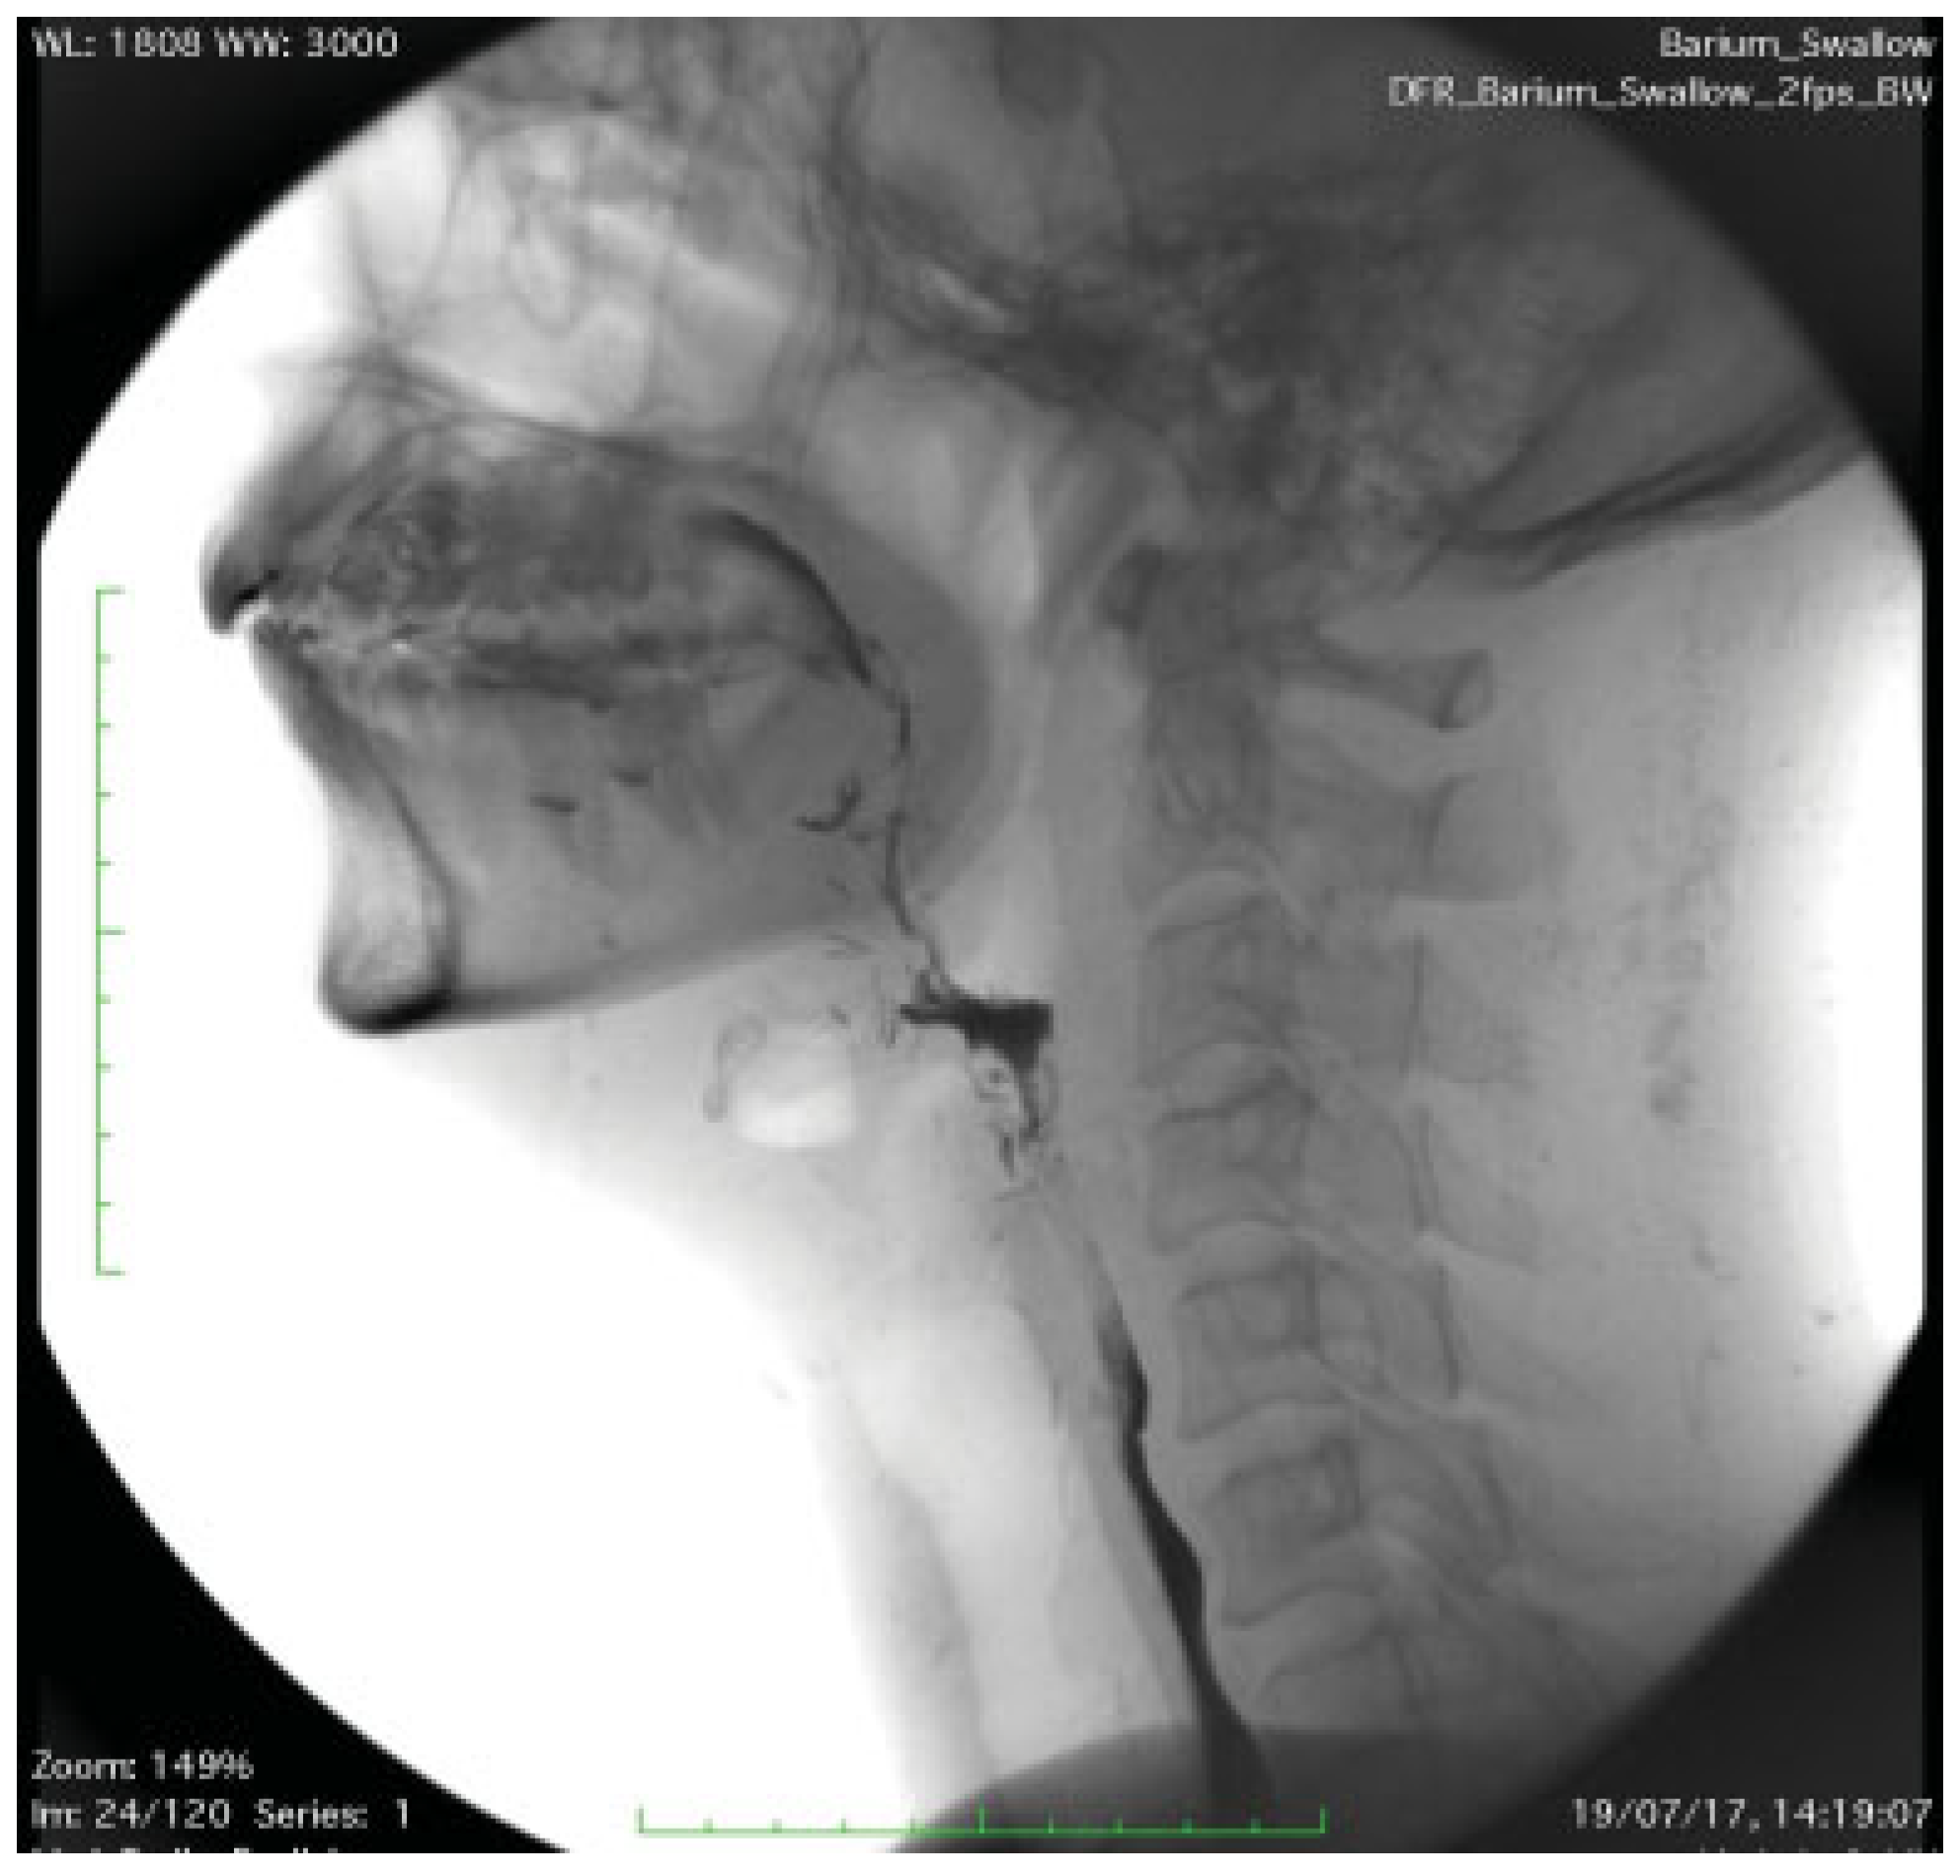

Postoperative Course

The patient tolerated the surgery and early postoperative course well. The tracheostomy was removed on the fifth postoperative day, and the patient could voice and articulate without much difficulty. A detailed swallowing assessment with videofluoroscopy and modified barium swallow (Figure 4) was performed on the sixth postoperative day, which showed near-normal swallow without signs of penetration or aspiration. He was initially commenced on a blended diet and then upgraded to a soft diet by the eighth postoperative day. A detailed speech and language assessment was performed a month after the surgery, which reported that the patient has intelligible speech with an occasionally noticeable difference and some reduction in accuracy of articulatory movements, but with the normal speed of articulation.

Figure 4. Modified barium swallow on the sixth postoperative day.